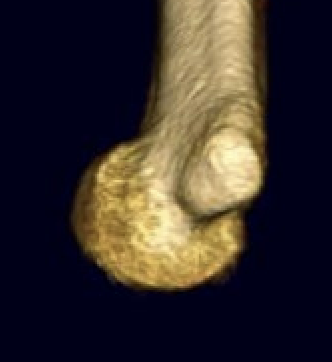

OTA / AO Classification

Type A: Extra-articular fracture

Type B: Partial articular fractures

Lateral condyle Medial condyle

Type C: Complete articular fractures

CT scan